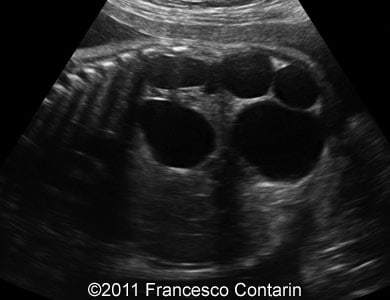

This is a case of a 24-year-old G3P2, with non contributive history, who was scanned at 32 weeks of gestation. Unilateral fetal multicystic kidney disease was found.

Images 1, 2, 3, and 4: The images show a series of longitudinal and transverse scans of the multicystic fetal kidney obtained at 32 weeks of pregnancy.